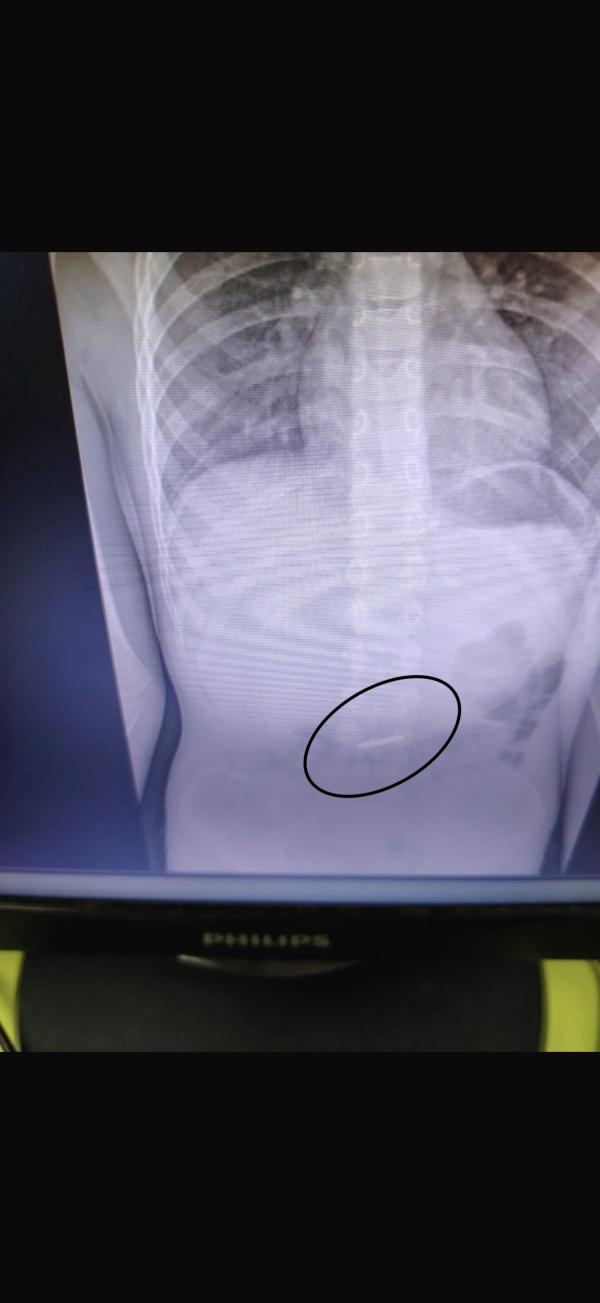

Но нет. Сегодня Андрей СЛУЧАЙНО проглотил 10-ти рублевую монету 🤦🏻♀️

На снимок съездили, будем отслеживать состояние и ждать и надеяться что все выйдет само.